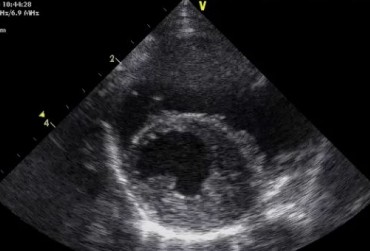

Zwężenie zastawki trójdzielnej jest jedną z form dysplazji pojawiającą się w różnym stopniu nasilenia (najczęściej łącznie z niedomykalnością zastawki) zarówno u psów, jak i u kotów. Cechami charakterystycznymi definiującymi zwężenie zastawki trójdzielnej są: obecność rozkurczowego wybrzuszenia (doming) płatków zastawki, zmniejszona ruchomość płatków, zmniejszona średnica ujścia zastawki. Mimo że zmiany morfologiczne aparatu trójdzielnego są typowe w przebiegu TVD i są znakiem rozpoznawczym tej choroby, nie są one zawsze bardzo silnie wyrażone i nie zawsze można mieć bezsprzeczną pewność diagnostyczną, bazując na badaniu echokardiograficznym [10]. Przypadki takie zdarzają się przede wszystkim u pacjentów, u których nie postawiono diagnozy we wczesnym etapie życia, a którzy pojawiają się na badaniu dopiero w starszym wieku z zaawansowanymi zmianami i niejednokrotnie z klinicznymi objawami prawostronnej niewydolności mięśnia sercowego i towarzyszącymi zaburzeniami w rytmie. W takich przypadkach obraz choroby może przypominać arytmogenną kardiomiopatię prawokomorową (arrhythmogenic right ventricular cardiomyopathy – ARVC) [1, 8]. Preekscytacja jest często obserwowana u ludzi z anomalią Ebsteina. U zwierzat, podobnie jak u ludzi, obecność dodatkowej drogi przewodzenia może nigdy nie prowadzić do rozwoju tachykardii nadkomorowej lub arytmia ta pojawiać się może dopiero w późniejszym okresie życia. Opisany przypadek jest przykładem pacjenta z dysplazją zastawki trójdzielnej i prawostronną niewydolnością serca będącą najprawdopodobniej konsekwencją tachykardii nadkomorowej.